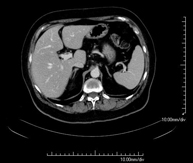

- Liver CT

Diagnostic test that involves obtaining high-definition anatomical two- and three-dimensional images of the liver using CT (computed tomography) equipment. The study must be performed before and after the use of iodinated contrast, carrying it out in different ‘hepatic phases’ to correctly assess all structures: hepatic parenchyma, intra- and extrahepatic bile ducts, gallbladder, hepatic vessels (hepatic artery, portal vein and suprahepatic veins) and adjacent structures (stomach, duodenum, inferior vena cava, pancreatic gland, etc.). This test is particularly useful in the study of liver damage, chronic liver disease, etc.